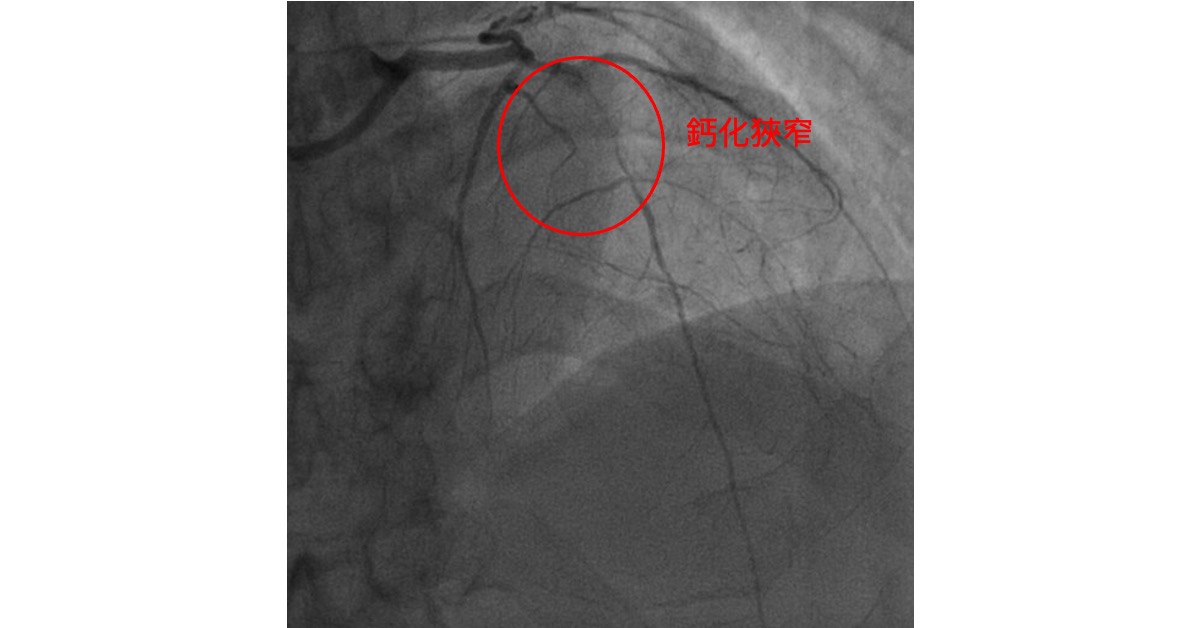

65歲的龍先生,之前一天需要抽1-2包菸,抽了近30年。3年前心肌梗塞,發現是右冠狀動脈的血栓完全阻塞,和左前降支的嚴重鈣化狹窄。 右冠狀動脈的支架順利地放好了,但是左前降支只能勉強將導絲通過,因為鈣化狹窄太厲害, 連只有1.5mm直徑的氣球都過不去。 於是暫且先處理到這個地步,接下來林醫師嚴格控制龍先生的三高, 也特別強調鹽分和水分控制, 這三年下來除了體力差一點之外,平常工作生活也都可以。 但是前一陣子寒流來的時候, 龍先生卻因為肺水腫住院, 心臟超音波之下,左心室射出分率從50%左右降到35%。 左前降支所供應的左心室前壁和心室中隔肌肉明顯地收縮特別無力。 左前降支如果打通應該對心臟功能會有幫助。 但是有鑒於上次的經驗, 要打通勢必須要額外的工具,還可能有有些許風險。

這一次林醫師也特別和國內專精與冠狀動脈慢性完全阻塞的專家跨院合作, 一起上台,希望能給病人最好的治療。 一開始就發現左前降支的鈣化依舊厲害(圖1.)。這次一樣勉強的用特殊導絲(Fielder XT-R)通過了左前降支的鈣化狹窄處,但是這次即使用上的特殊的旋轉導管(Corsair-Pro)還是沒有辦法將任何氣球通過。 於是專家想出了一招, 就是在 冠狀動脈鈣化狹窄處用電燒!

圖1.